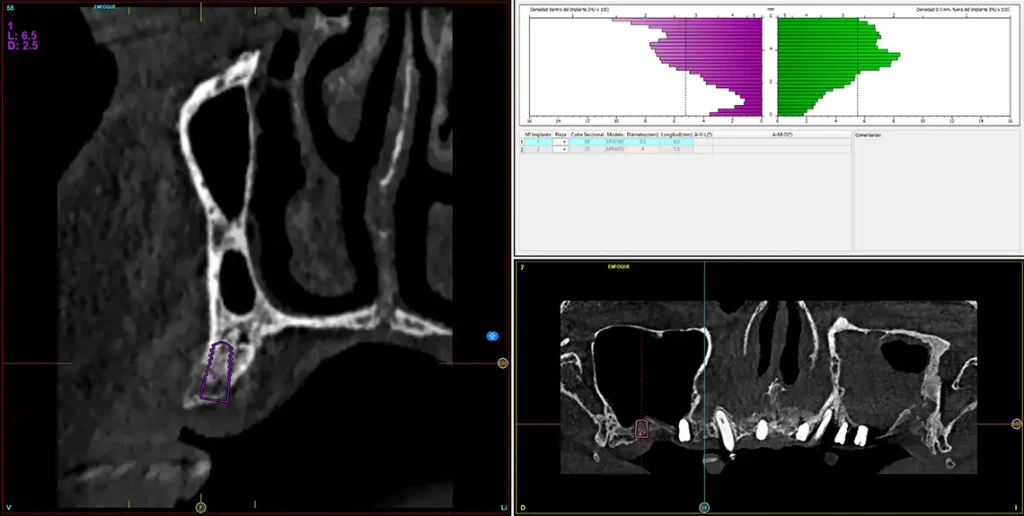

En la zona correspondiente a la pieza 24, tenemos una atrofia extrema también pero en este caso en sentido vertical, con una cresta residual de 3,1 mm de grosor, como podemos ver en el corte seccional del cone-beam (fig. 11). En este caso se planifica la colocación de un implante de 2,5 mm de diámetro y 6,5 mm de longitud (con plataforma reducida de 3 mm -plataforma 3.0, biotechnology institute-) (fig. 12). Igualmente, en la zona anterior de la premaxila, tenemos una situación muy similar donde el volumen óseo es reducido, incluso más que en la zona del segundo cuadrante y, por ello, optamos también por implantes de 2,5 mm de anchura y plataforma de 3 mm (figs. 13-16).

Fig. 11. Corte de planificación de la zona correspondiente a la pieza 24, que presenta una atrofia ósea en anchura extrema con 3,1 mm de anchura residual.

Fig. 12. Planificación del implante de 2,5 mm de diámetro y 6,5 mm de longitud que será colocado en la zona.